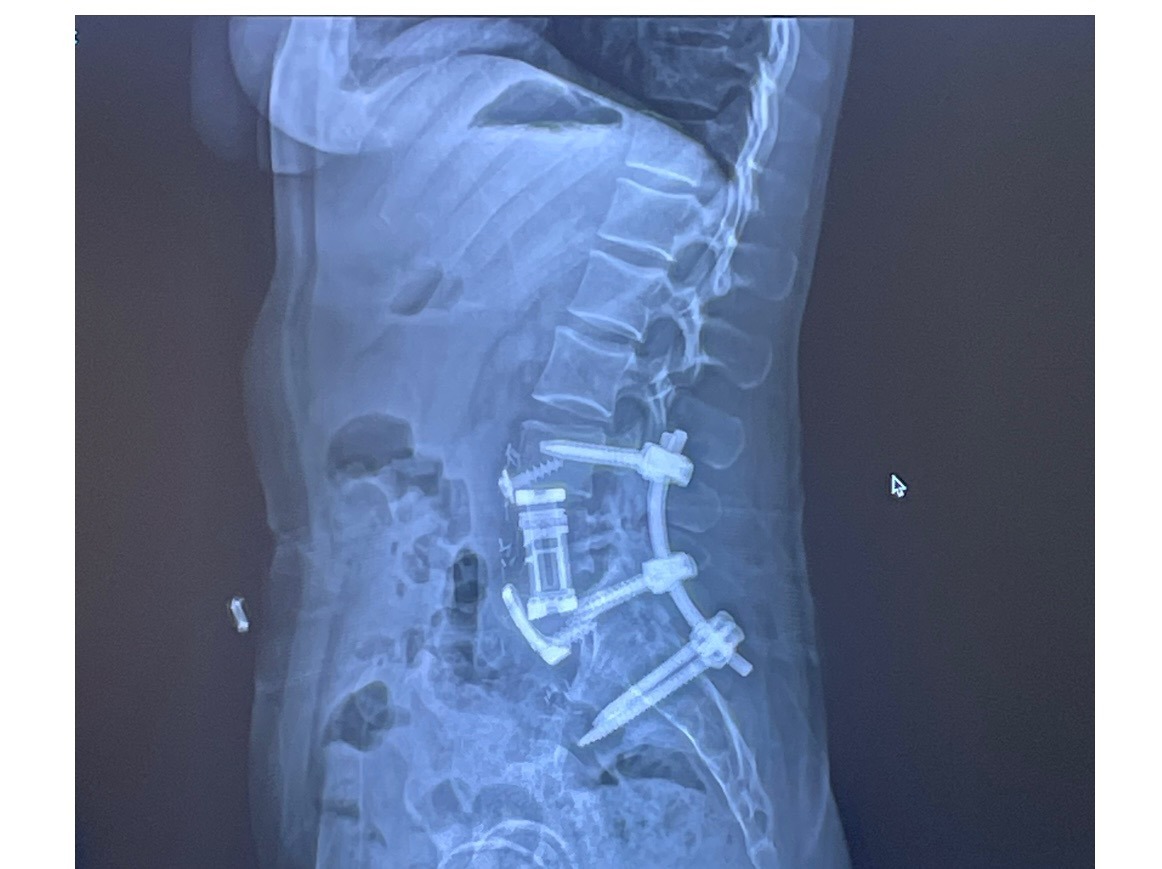

In December 2024, Caela underwent two major surgeries to remove the tumor and stabilize her spine with rods and screws. She fought hard through recovery, but in April 2025, the tumor returned—and 4mm of bone is already gone.

Now, she faces a second complex surgery with a team of top specialists, including a world-renowned bone tumor expert. During the operation, doctors will attempt to remove the mass and biopsy for osteosarcoma. There are still many unknowns—possible radiation, additional rods, and months of recovery ahead.